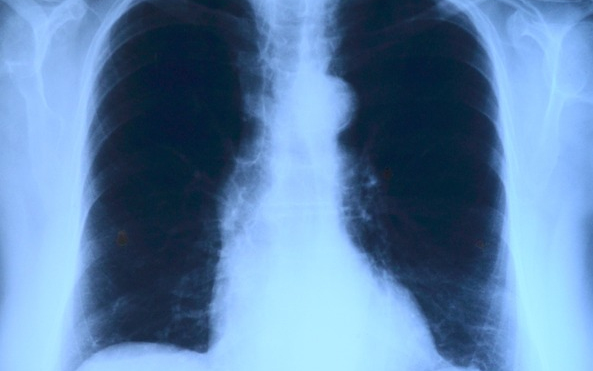

Elvégezték az országban az első tüdőverőér-tágítást

Az országban elsőként a Debreceni Egyetem Klinikai Központjában végeztek tüdőverőér-tágítást - közölte a felsőoktatási intézmény sajtóirodája kedden az MTI-vel.

A nemzetközi orvoscsoport múlt hét szombaton két betegnél hajtotta végre a beavatkozást, amellyel a tüdőerek magas vérnyomását csökkentették. Mindkét páciens krónikus thromboembóliás pulmonális hipetróniában szenvedett, amely súlyos nehézlégzést, kisebb fizikai terhelhetőséget és akár eszméletvesztést is okozhat. Az első hazai ballonos pullmonális értágítást (BPA) Irene Lang professzor, a bécsi Allgemeines Krankenhaus (AKH) kórház II. Belgyógyászat-Kardiológiai osztályának vezetője és tanítványa, Christian Gerges végezte a debreceni kardiológiai és szívsebészeti klinika intervenciós kardiológusainak közreműködésével - olvasható az egyetem közleményében.

A nagy szakértelmet és türelmet igénylő, komplex katéteres eljárást egy 59 éves férfinál és egy 82 éves nőnél végezték el. A 2-3 órás beavatkozás során a tüdő véráramlását akadályozó vérrögöket ballonnal kitágították, így az áramlási akadály mérséklődött, a tüdőerekben pedig csökkent a nyomás, ezzel együtt a szív terhelése is.

A módszert a világon először 1988-ban alkalmazták, az első nagyobb betegszámú vizsgálatot 2001-ben publikálták, 2004-től pedig elsősorban Japánban tökéletesítették az eljárást, amely azóta az Egyesült Államokban, Norvégiában, az utóbbi évtizedben pedig Európa más országaiban is egyre elterjedtebb lett.

A közleményben hangsúlyozzák: A Debreceni Egyetem szakemberei bíznak benne, hogy az eljárást Lang professzor és munkatársai, valamint a Klinikai Központ orvosai segítségével sikerül meghonosítani Magyarországon is. A betegek életében ugyanis jelentős változást hoz a BPA-beavatkozás, a kezelés következtében csökkennek a fulladásos panaszok és nő a fizikai terhelhetőség.

A módszer nagy előnye a rövid felépülési idő, hiszen a műtét utáni kétnapos intenzív megfigyelést követően a betegeket akár már a harmadik nap hazaengedhetik. Az első magyarországi ballonos tüdőverőér-tágításon átesett betegek jól vannak, kedden már el is hagyhatták a klinikát - zárul az egyetem közleménye.